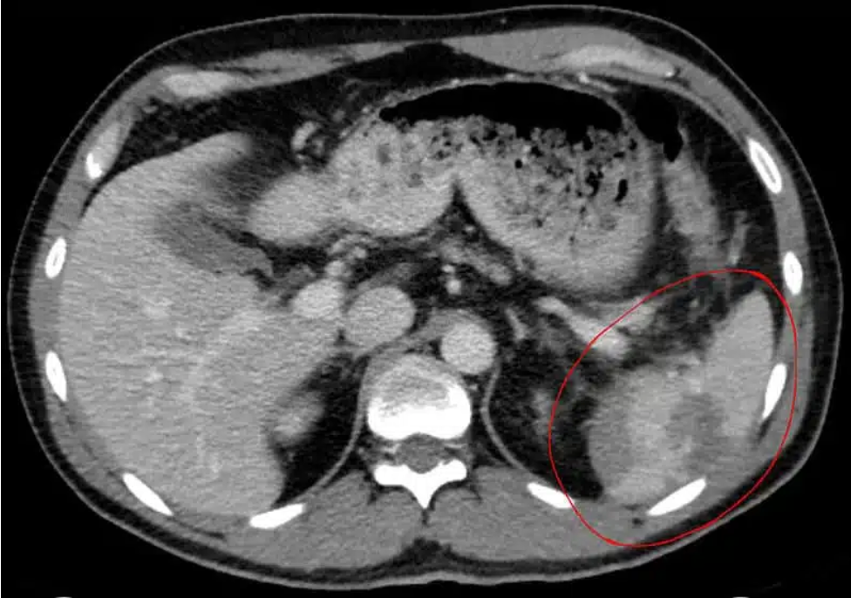

Miltraume:

Diagnose?